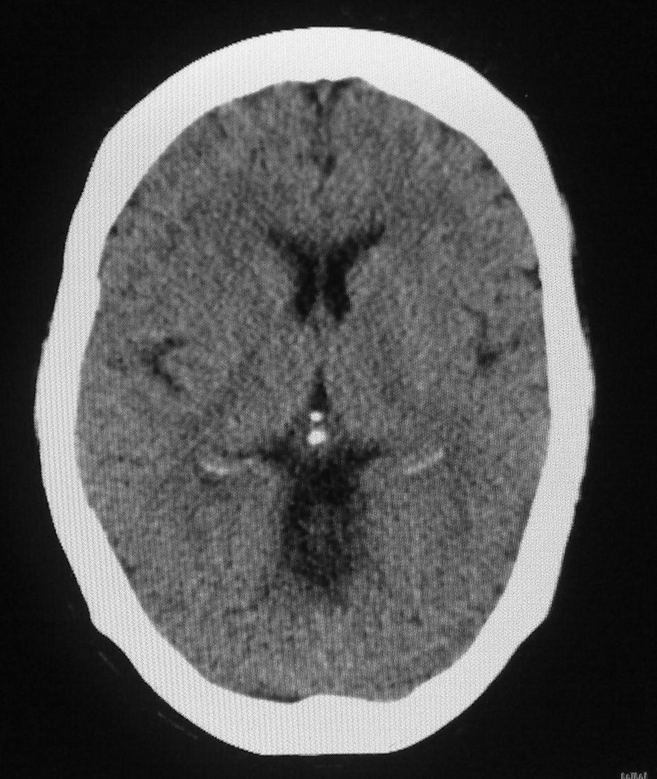

女,46岁,走路有时向一侧偏斜。是小脑萎缩吗?

小脑脑沟增多加深      为小脑萎缩引起的共济失调

小脑脑沟多于四条即为增多,又见加深,所以支持小脑萎缩。

从图像上看的确有轻度小脑萎缩征象,但患者才46岁,有外伤史吗?

小脑萎缩可能性大,建议mri检查。

小脑轻度萎缩